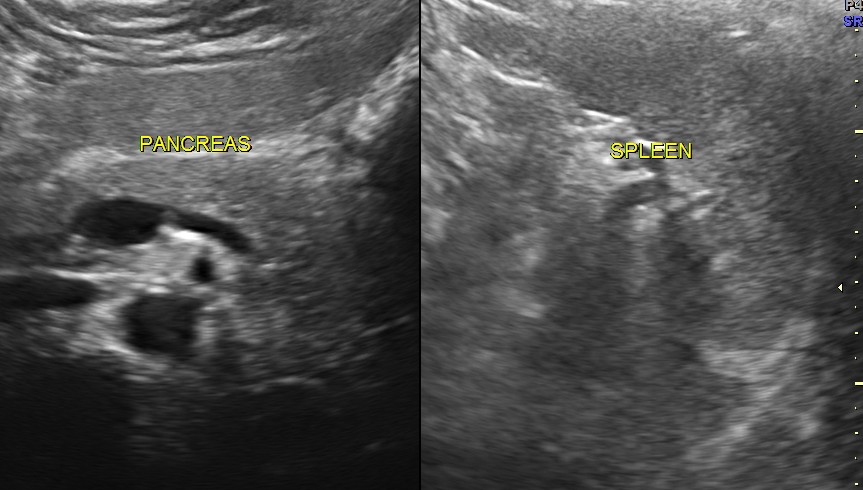

Ultrasound revealed normal liver, gall bladder, pancreas, spleen ,post menopausal shrunk uterus and normal right kidney.